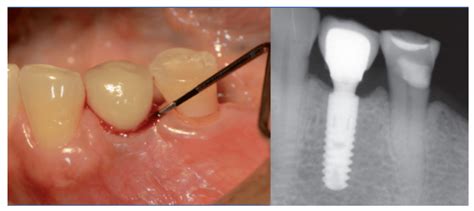

Diagnóstico de la inflamación periimplantaria

El diagnóstico de la inflamación en los tejidos que rodean un implante dental es crucial para determinar la presencia de condiciones como la mucositis o la periimplantitis. El diagnóstico de la periimplantitis lo realiza el odontólogo o periodoncista mediante una combinación de evaluación clínica en la boca y pruebas de imagen (radiografías principalmente).

- Radiografías: Las radiografías son una herramienta fundamental para visualizar la posición del implante y la calidad del hueso que lo sostiene.

- Sondaje periimplantario: La evaluación de la bolsa periimplantaria es clave para determinar la presencia de inflamación.